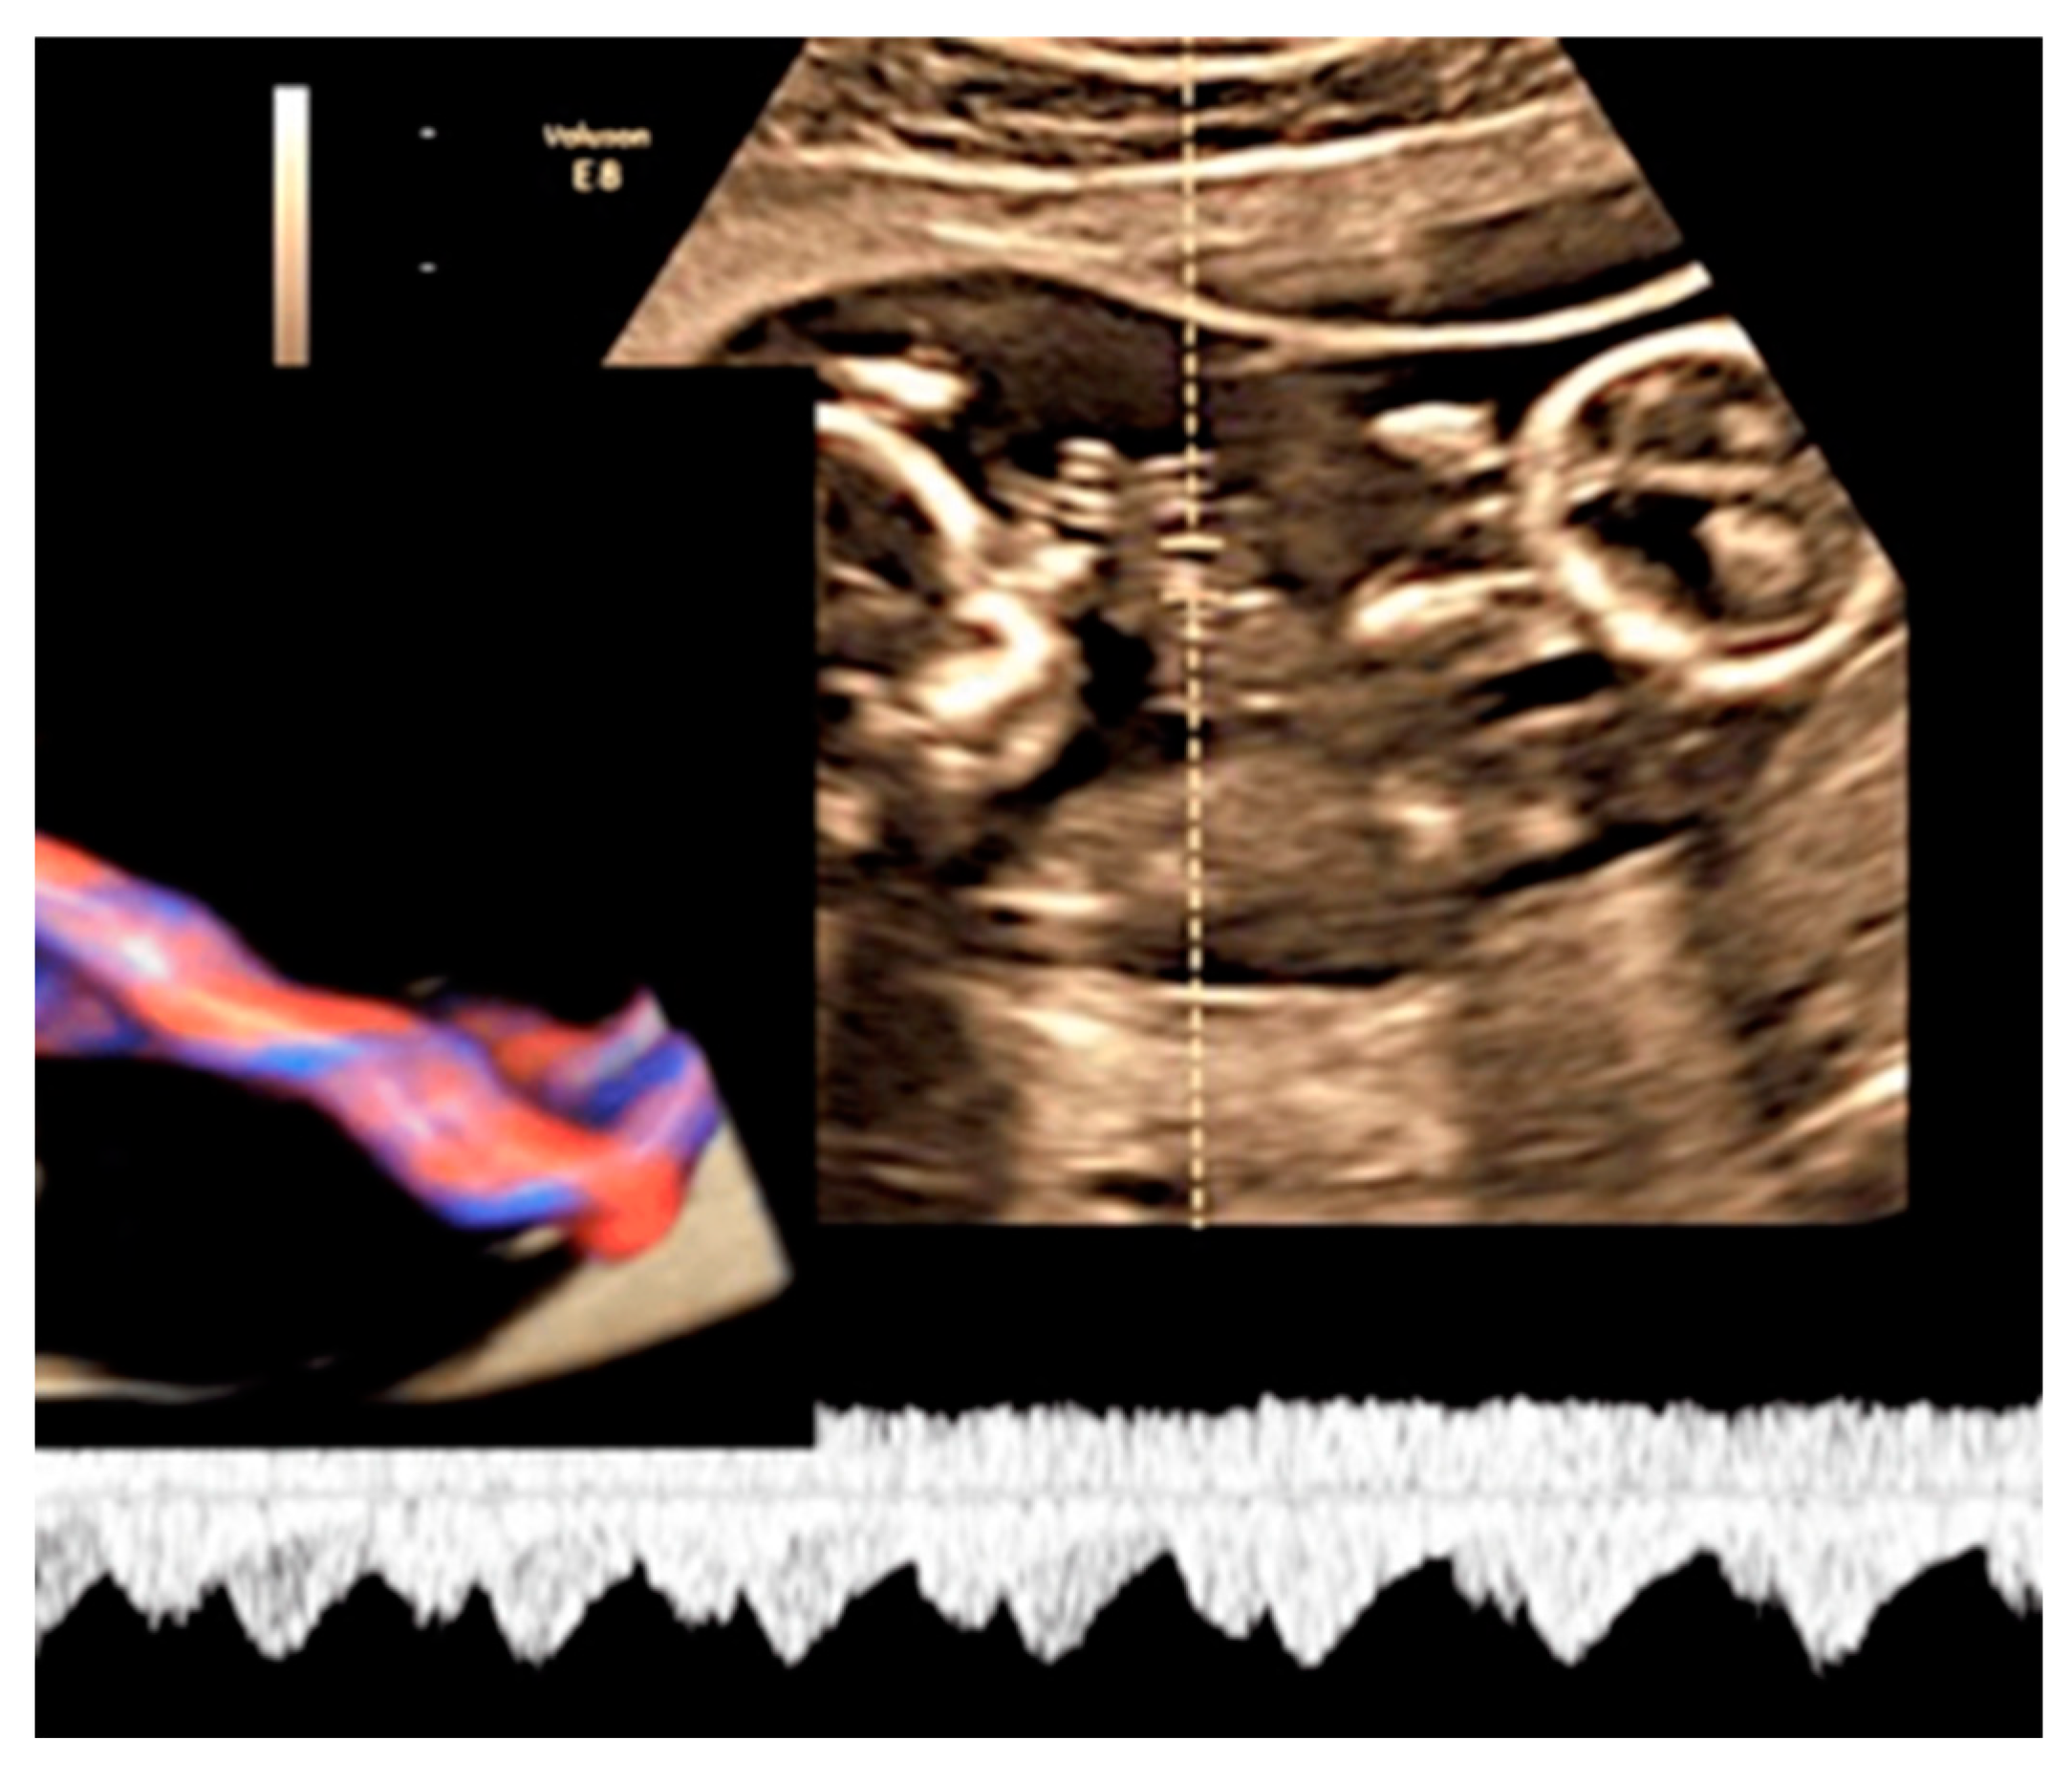

3.2.6. Umbilical Cord Entanglement

3.2.7. Umbilical Cord Hemangioma